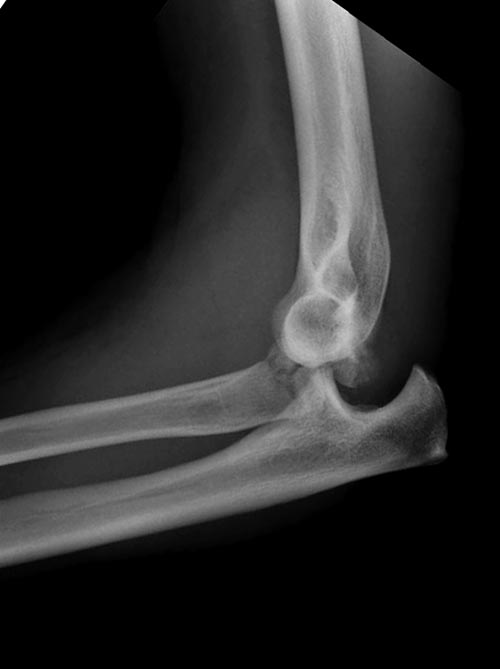

Один снимок всего? Может КТ-срезы какие-нибудь есть, R-снимки без гипса фас/профиль? По этому снимку вроде бы и нет вдавленного перелома. Суставная поверхность расколота - это да, но импрессии не увидел. Мы бы попытались сохранить головку.

Вместе обычных простых рентгенограм, участились злоупотребления дорогими исследованиями. Хотя многие переломы, даже внутрисуставные, можно увидеть на обычных рентген снимках. Негативный рентген при исследовании локтевого сустава не означает отсутствие перелома. Если имеется “fat pad sign”, характерный симптом для внутрисуставных повреждений, тогда можно ставить диагноз перелом головки луча! Гематома внутрисуставного перелома смещает жировое тело и на боковом снимке проявляется в виде “паруса”.

Для выработки показаний достаточным бывают стандартные снимки, но иногда требуется косая рентгенограмма по Coyle. И для подтверждения смещений и оценки внутрисуставных фрагментов рекомендуется КТ, а 3D снимки показывают только поверхность, т.е. получается общая картина. МРТ дает возможность оценить состоянии связок.